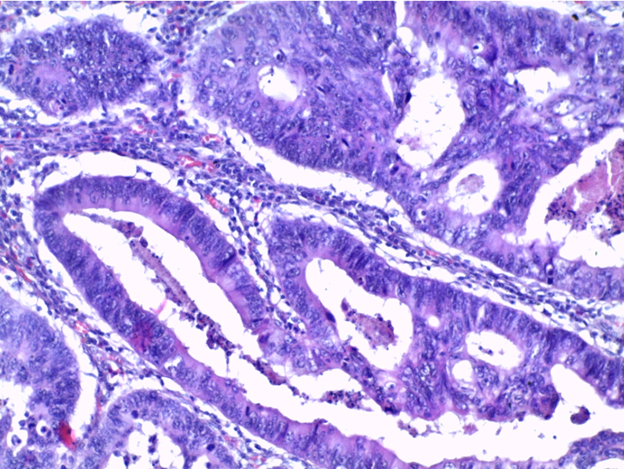

Препарат № 100.

АДЕНОКАРЦИНОМА ТОЛСТОЙ КИШКИ

Окраска: гематоксилин-эозин

В одной части препарата обнаруживаем нормальное строение слизистой оболочки. На большем протяжении слизистая представлена опухолевой тканью, паренхима ее состоит из причудливых ветвящихся железистых трубочек, эпителий которых полиморфный; ядра крупные, сочные, гиперхромные с множеством митозов. Такие же железистые образования видны в подслизистом и мышечном слоях стенки. В строме опухоли воспалительные инфильтраты, очаговые кровоизлияния.